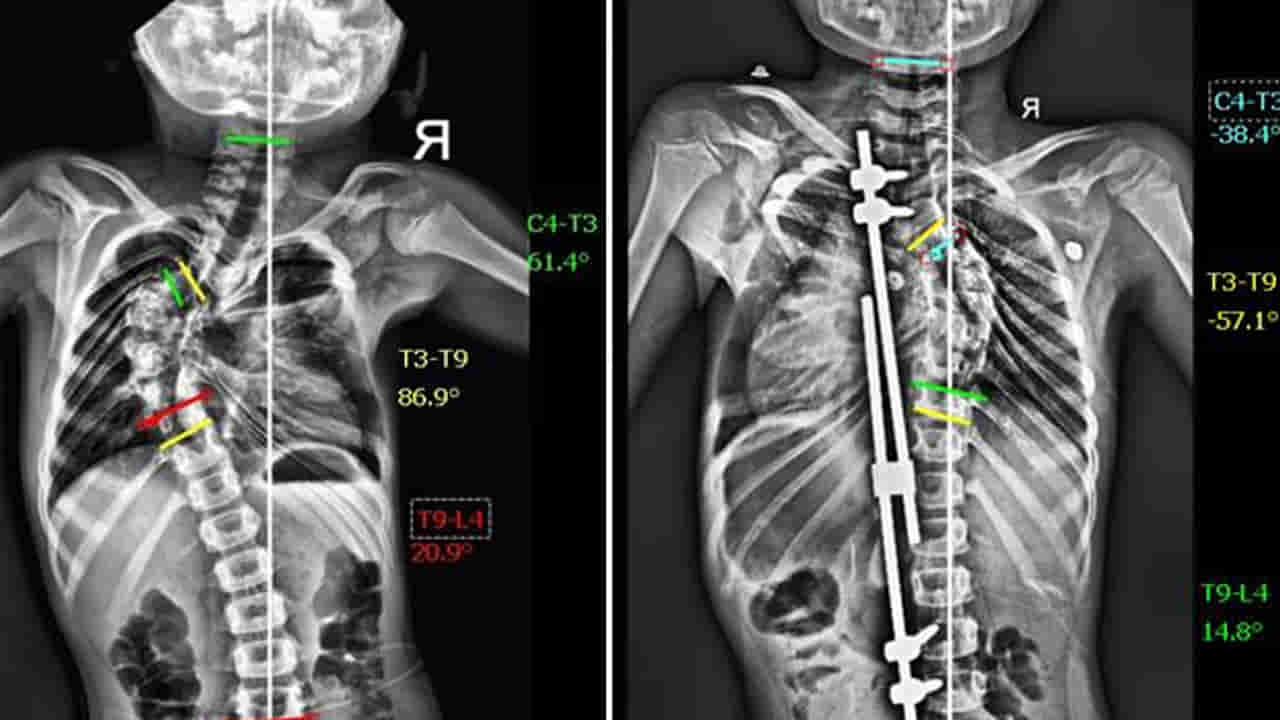

పాపకు పరీక్షలు చేయగా, ఆమె వెన్నుపూస 86 డిగ్రీల వక్రతతో ఉన్నట్లు తేలింది. ఇది “థొరాసిక్ స్కోలియోసిస్” అనే వ్యాధి, దాన్ని నిర్లక్ష్యం చేస్తే గుండె, ఊపిరితిత్తులకు సమస్యలు కలగవచ్చు. డాక్టర్ విద్యాధర రోబోటిక్ టెక్నాలజీ సాయంతో “గ్రోత్ రాడ్ సర్జరీ” చేయాలని సూచించారు. ఇది కేవలం వెన్నుపూస వక్రతను సరిచేయడం కాకుండా, అది సహజంగా పెరగడానికి కూడా సహాయపడుతుంది.

మే 1, 2025న ఆద్యకు సర్జరీ జరిగింది. అత్యాధునిక రోబోటిక్ టెక్నాలజీతో, ఆమె వెన్నుపూసను సున్నితంగా సరిచేయడం జరిగింది. శస్త్రచికిత్స పూర్తయిన మూడు గంటల్లోనే ఆద్య సపోర్ట్తో నడవగలిగింది. రెండు రోజుల్లోనే ఆమె ఆసుపత్రి నుంచి డిశ్చార్జ్ అయింది.